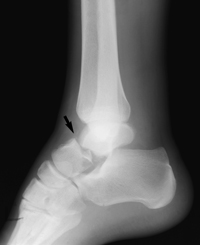

An x-ray of a talus neck fracture.

Reproduced from Johnson TR, Steinbach LS (eds): Essentials of Musculoskeletal Imaging. Rosemont, IL American Academy of Orthopaedic Surgeons, 2004, p. 605.

Fractures occur in all parts of the talus bone. Most commonly, the talus breaks in its mid-portion, called the "neck." The neck is between the "body" of the talus, located under the tibia, and the "head," located further down the foot.

The talus often breaks in the mid-portion — or "neck" — of the bone. This illustration shows a displaced talus neck fracture.